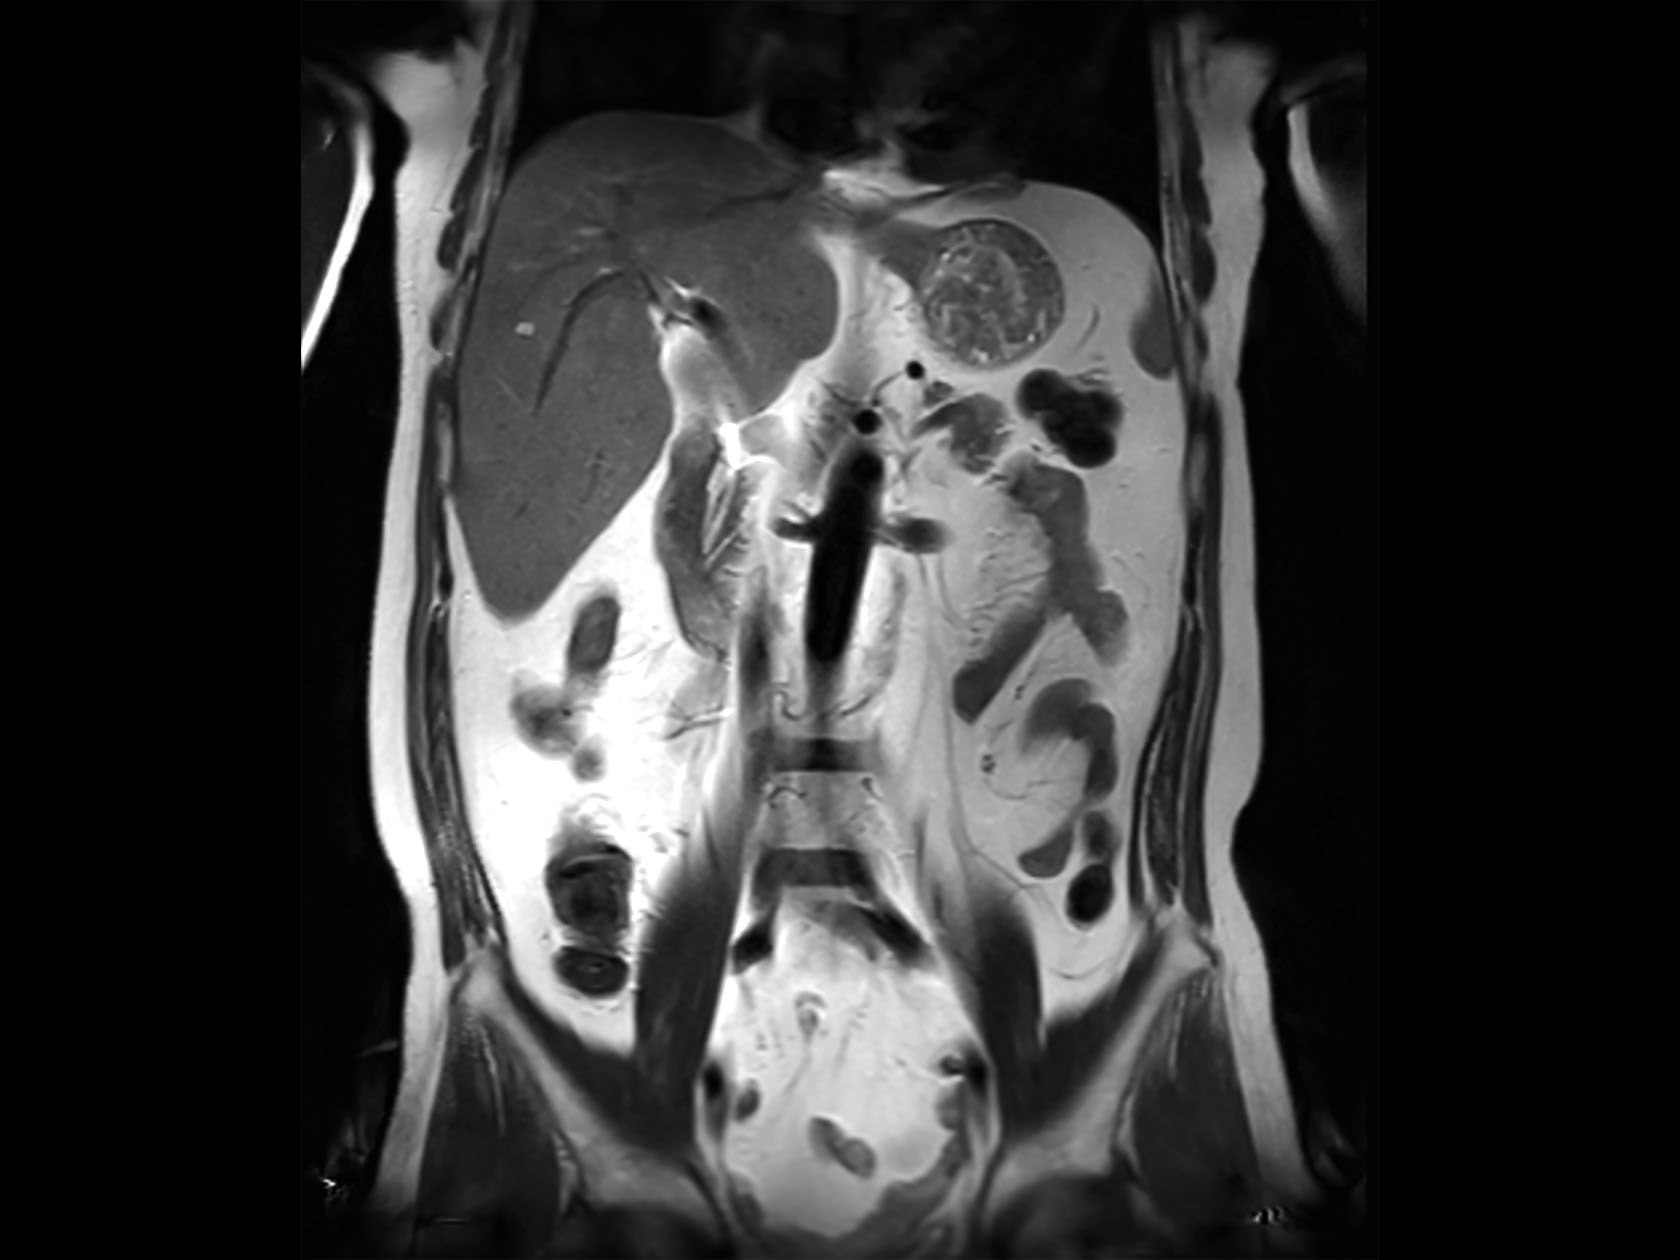

Coronal T2w TSE